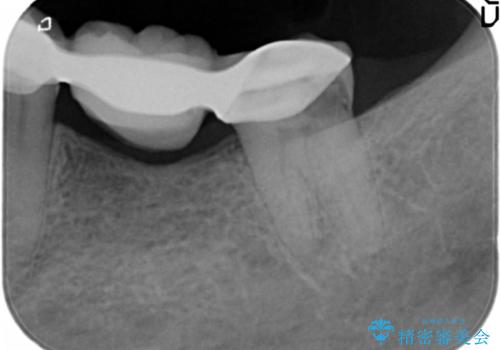

精査したところ、ブリッジの支台歯となっている左下の奥歯(左下7)は大きなう蝕により神経が死んでいました。

根管治療後、メタルボンドブリッジによる補綴治療を行いました。

クラウンの種類:メタルボンドクラウン エコノミー